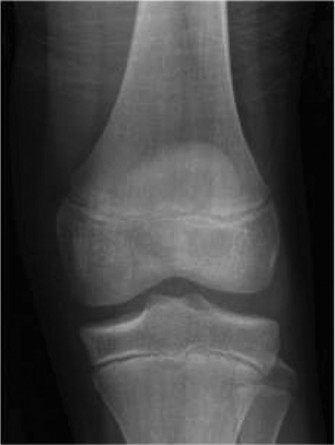

CASE 5 A 24-year-old graduate student twists her knee while walking in high he…